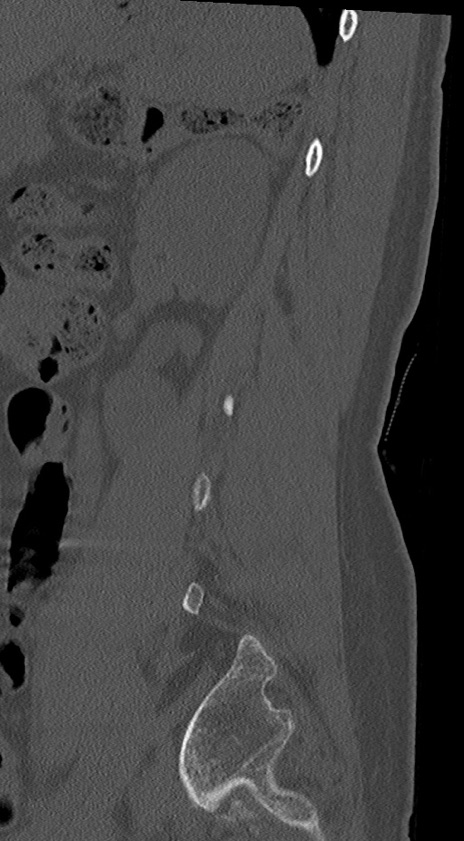

【整形】TIPS症例4 腰椎CT(矢状断像)

腰椎CT